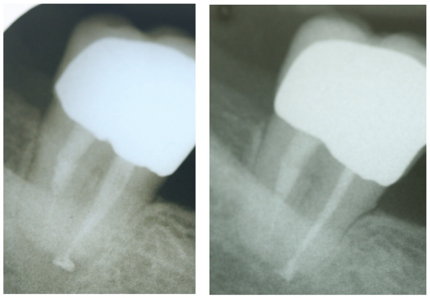

Ziel unseres recall´s ist es, alle auswärtigen Patienten mindestens einmal nachzuuntersuchen. Und zwar nach einem halben Jahr. Das Gros der Patienten ignoriert unser Schreiben, nur eine Minderheit meldet sich letztendlich für einen Kontrolltermin an. Es sind meist die Patienten, die nicht vollständig beschwerdefrei sind, sondern unter unbestimmten, subakuten Missempfindungen leiden. In den wenigsten Fällen lässt sich ein morphologisches Korrelat dazu darstellen. Die Zähne stehen klinisch ordentlich da, die Kontrollaufnahmen sind ohne Befund. In dem ein oder anderen Fall würde ich die Sache gerne weiterverfolgen – die Aussicht auf ein DVT wird eher seltener goutiert. Ein weiterer Arzttermin? Kosten? Nun, so schlimm ist´s auch wieder nicht. Interessant ist für mich der folgende Ansatz, über den ich bei den sehr geschätzten Wurzelspitzern gelesen habe.